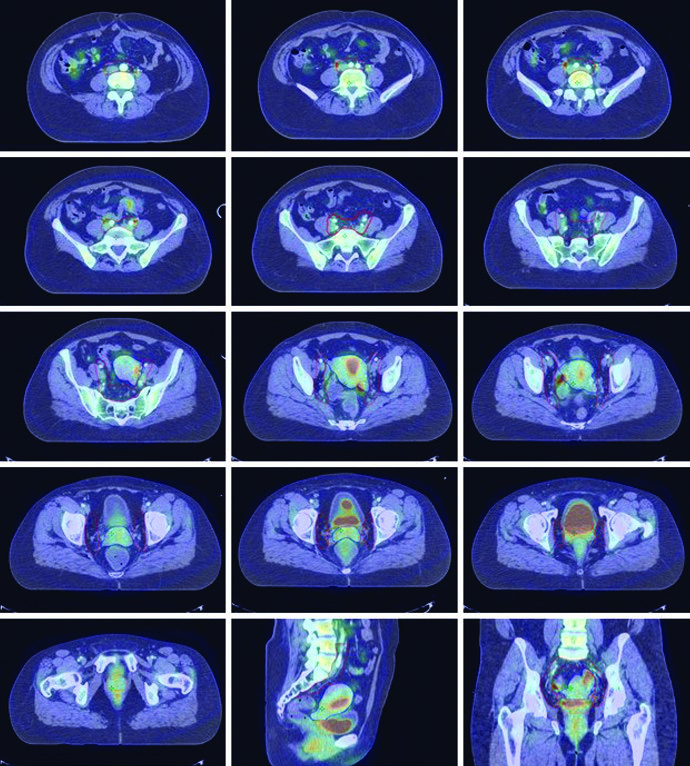

A fusão do PET/CT pré-tratamento com a TC de simulação é recomendada para auxiliar no delineamento do volume tumoral bruto (GTV). Diretrizes internacionais de consenso para contorno em casos de cérvice definitiva já foram publicadas, e casos-amostra interativos estão disponíveis em plataformas educacionais como o eContour.

A IMRT demonstrou reduzir toxicidade GI e hematológica, e pode melhorar toxicidade urinária relatada pela paciente. O PET/CT pode ser usado para segmentar sub-regiões ativas de medula óssea, onde acúmulo de dose correlaciona-se com maiores taxas de toxicidade hematológica. Poupar medula metabolicamente ativa com IMRT reduziu neutropenia e melhorou tolerância à quimioterapia em ensaios clínicos prospectivos.